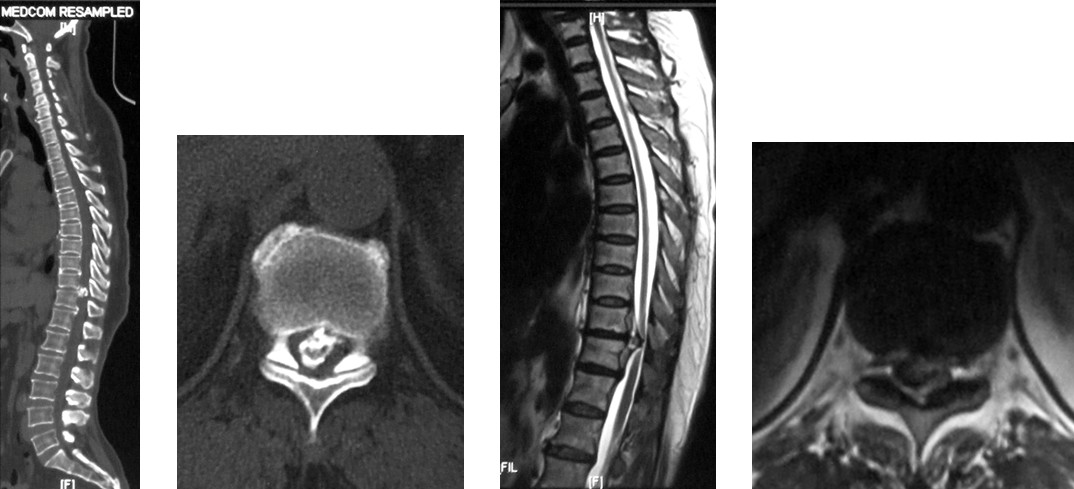

4. 典型病例:病例1,患者男性,40岁,司机。主因胸腰背部疼痛3年,肛周麻木、性功能减退并伴双足下垂2年,症状加重且二便肥力、无法工作1年入院。入院查体:一般情况良好,体胖、体重105kg。步态不稳,步行缓慢。胸腰段脊柱背部轻压痛,无放射。双侧股四头肌力IV级,双侧胫前肌力I级,双侧足下垂。鞍区感觉减退,无病理征。双侧跟、膝腱反射消失。血化验检查正常。X线平片显示T12~L1椎间隙明显变窄。CT显示T12~L1椎间盘突出并椎体后缘离断。MRI显示T12~L1椎间盘呈中央型突出,椎管狭窄,脊髓明显受压变形。入院诊断:T12~L1椎间盘突出症伴椎体后缘离断,马尾神经损害。术前检查完成后,在气管插管全麻下行上述经极外侧入路T12~L1椎间盘切除手术治疗,整个手术过程顺利,无术中及术后并发症发生,术后1周顺利出院。出院时,其双侧股四头肌、胫前肌肌力已分别恢复至V级和III级;鞍区感觉减退亦有明显好转。术后显示T12~L1突出之椎间盘及离断之椎体后缘已被完全切除,椎间融合器及椎弓根螺钉位置佳,脊柱局部生理曲度良好(图2a~2l)。病例2,女性患者,59岁。主因间歇性跛行,双下肢无力3年入院。入院诊断:T11椎体后上缘骨软骨瘤。以与病例1相同的术式行椎体骨软骨瘤的彻底切除(图3a~3l),无手术并发症发生,术后患者下肢症状明显改善。

图2a~2d. 典型病例1患者术前CT, MRI均显示为T12~L1椎间盘突出合并椎体后缘离断, 致椎管狭窄, 脊髓明显受压